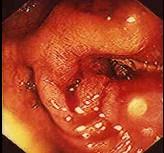

问题 女性,50岁,反复腹泻,黏液脓血便10年,加剧2月;近来明显消瘦;既往呈确诊为溃疡性结肠炎。现服用柳氮磺胺吡啶症状无缓解,肠镜检查如图,首选治疗措施为 ( )

选项 A、口服异烟肼、利福平 B、手术治疗 C、柳氮磺胺吡啶 D、静脉滴注氢化可的松 E、口服氟哌酸

答案 B